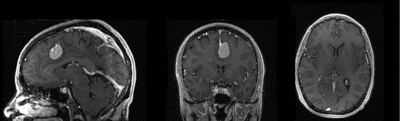

Slicer Registration Use Case Exampe #2: Inter-subject Brain MRI: axial T1 Tumor Growth Assessment

This is a classic case of change assessment. We want to know if the tumor changed since last exam.

MRI, brain, head, intra-subject, T1, tumor growth, meningioma, change assessment

reference/fixed : T1 SPGR , 0.9375 x 0.9375 x 1.4 mm voxel size, axial, RAS orientation.

moving: T1 SPGR , 0.9375 x 0.9375 x 1.2 mm voxel size, sagittal, RAS orientation.- Content preview: Have a quick look before downloading: Does your data look like this? Media:RegUC2_lightbox.png

- result screenshots (compare with your results)

- result evaluations (metrics)